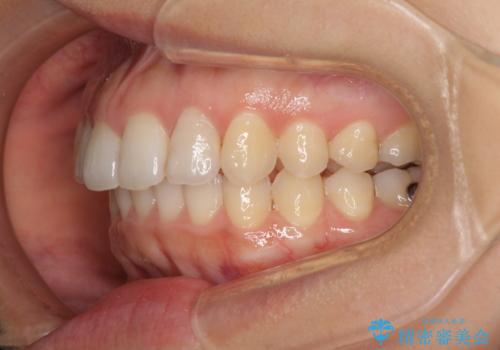

インビザライン矯正で前歯のデコボコを改善

- 前歯のデコボコを気にして来院された患者様です。

目立たないことを最優先にしたいとのことで、デコボコは軽度であったことから、インビザラインにて矯正治療を行うこととしました。

骨格的に下顎骨が左にずれており、上下の正中一致は困難ではありましたが、IPR(歯と歯の間を削る)や後方への移動など組み合わせて、できる限り改善しました。

インビザラインはマウスピースを外している時間が長いと、長期間使用しても前歯のデコボコはあまり改善されません。こちらの患者様は治療期間が長くなり、装着時間が短くなってしまったことで、気になる部分の改善により長期間を要するようになってしまいました。